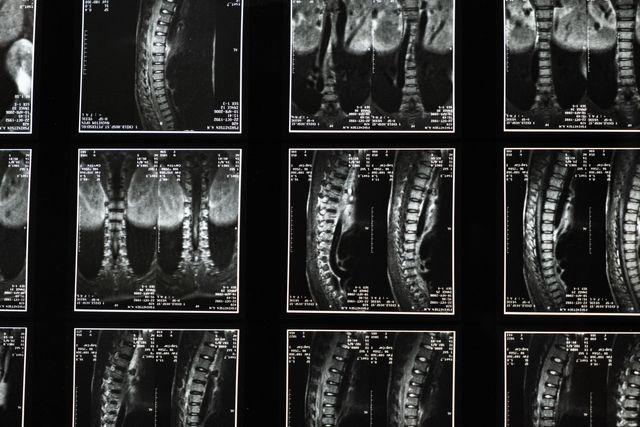

Navigate through our brain, spine and neurovascular pages to learn more about specific conditions and the innovative neurosurgery technology we use to treat them. Each page provides you with detailed information on tumors, strokes, spinal stenosis and more, with helpful links that can better inform you and your loved ones.

IGEA Brain, Spine, Pain & Orthopedics is a world-class center of neurosurgical excellence that delivers information for each field of practice to patients in New Jersey and across the nation. Select any category below to learn more about your condition and the leading edge surgical systems we use to help guide you into a state of health and well-being.